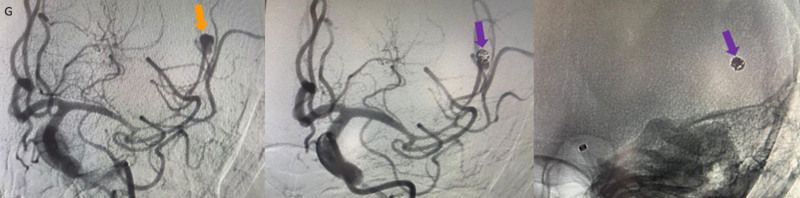

- DSA görüntülemede (G) sol MCA M2 segmentinde anevrizmatik dolum fazlalığı izleniyor (ok). Bu anevrizmaya eş zamanlı koil işlemi yapılıyor (oklar) ve işlem sonrası kontrol BT anjiografi görüntüsünde (H) metalik koil materyali izleniyor (ok).